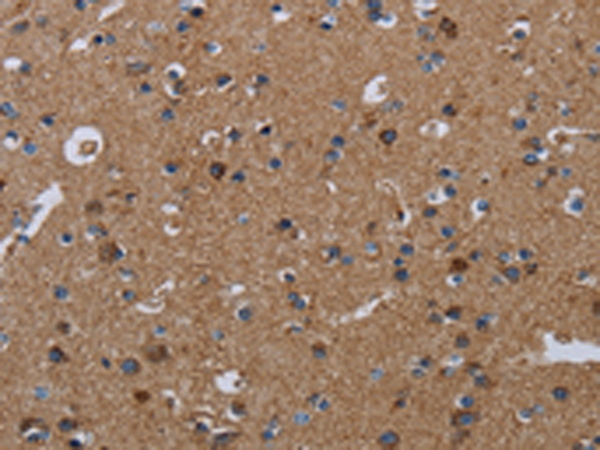

分类: 科研抗体货号: P08539别名: Bex; NADE; HGR74; NGFRAP1; DXS6984E应用: IHC反应种属: Human